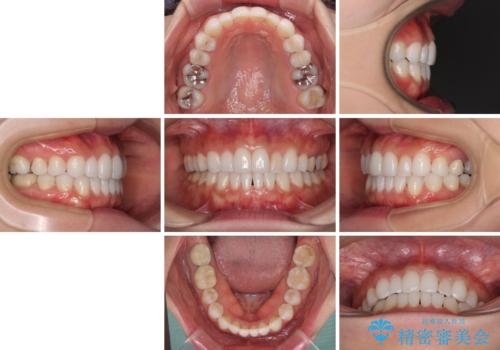

- 前歯が気になるとのことで来院された患者様です。

歯列不正は軽微であったため、インビザライン・ライトにより、費用を抑えて矯正治療を行うこととしました。

短期間で気になる前歯の歯列を改善することができました。